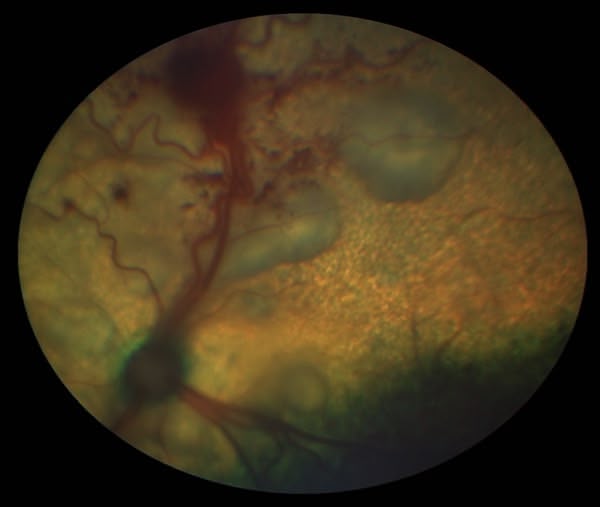

Figure 1